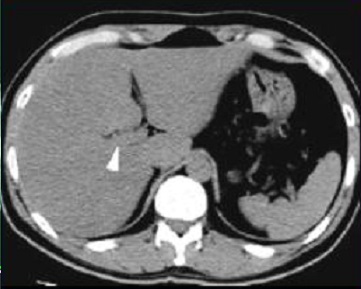

Image TDM de

steatose :

Normalement la densite du foie est

plus hyperdense de 6-12 UH que la rate . Par

infiltration de la graisse des cellules

hepatiques , la parenchyme devient fortement hypodense

( 30-40UH ) par rapport a une foie

normale ( normalement 50UH ) . Le foie est

steatosique quand sa densite en moindre 10 UH que la

rate . : |

Image TDM sans preparation :

Normalement la densite du foie 50UH et la rate est

40 - 45 UH . |

En cas steatose du foie la

densite du foie est moins dense 10UH que la rate |

Image TDM d'une steatose du

foie : Le foie est hypodensse que la rate . Gradient

normal sans injection foie/rate =10UH |